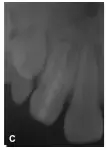

2開(kāi)髓,揭頂,大量膿液從根管內(nèi)滲出,探查根管發(fā)現(xiàn),內(nèi)陷的牙釉質(zhì)與正常牙本質(zhì)緊密相連,擴(kuò)大針無(wú)法從二者之間進(jìn)入主根管,而通過(guò)內(nèi)陷的中央管腔可以到達(dá)主根管(圖1B)。拔髓不成形,通暢根管,生理鹽水沖洗,CP開(kāi)放引流,囑口服阿莫西林0.25g/Tid。沖洗換藥1次/3d,換藥2次后右上唇及頜面部腫脹消失,疼痛緩解。內(nèi)陷根管封Vitapex 1周后,30號(hào)擴(kuò)挫,Vitapex充滿內(nèi)陷根管,磷酸鋅水門(mén)汀封洞。以后前3個(gè)月每隔1個(gè)月更換Vitapex1次(圖1C),后12個(gè)月每隔3個(gè)月更換Vitapex 1次。

圖1B:2內(nèi)陷根管插牙膠尖片;C:2 Vitapex充填內(nèi)陷根管5個(gè)月后根尖暗影消失;